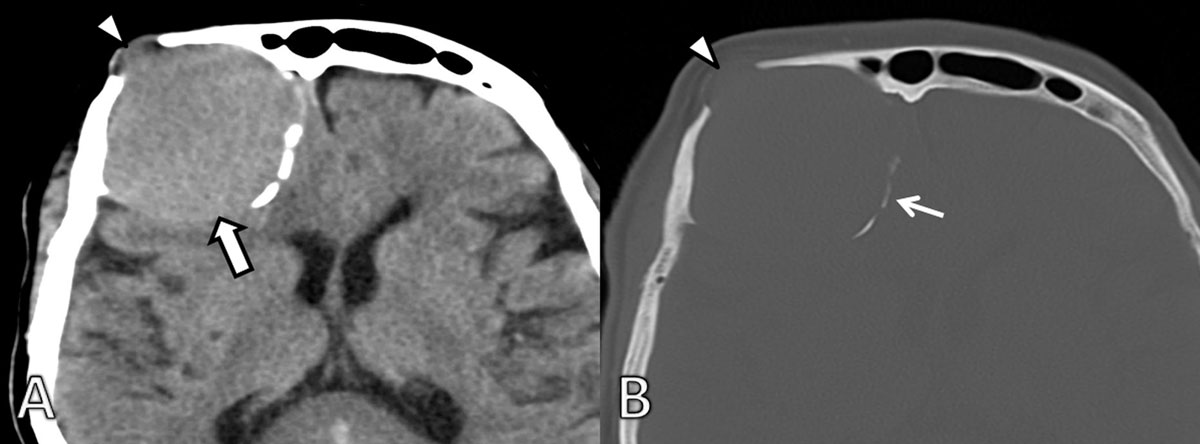

A 72-year-old woman was admitted at the emergency department after a fall. A large bump was noted on her left forehead and subsequently a non contrast-enhanced CT of the head was performed (Figure 1A). The CT scan revealed a large extra-axial slightly hyperdense mass on the right frontal bone. There was expansion of the frontal bone with thinning of the internal and external tables and even some focal cortical discontinuities (Figure 1B).

Figure 1

Initial axial non-enhanced CT. A. Soft tissue and B. bone window show a slightly hyperdense mass to gray matter (arrow) located at the right frontal bone causing scalloping of the internal and external table (arrowhead). There is focal discontinuity of the external and internal table. Remnants of the expanded frontal bone (thin arrow) can be seen medially.